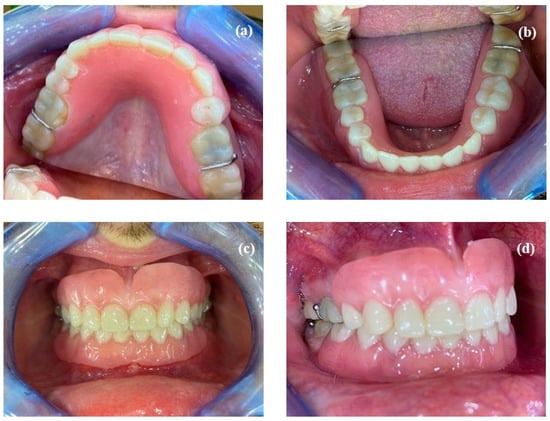

- Fabrication of definitive removable partial dentures: the definitive prostheses were fabricated using the conventional technique from functional impressions. The patient’s new smile is shown in Figure 10.